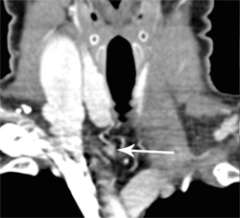

Figure 1a. Parathyroid 4D-CT showing a parathyroid adenoma in an abnormal position within the carotid sheath, missed during a prior surgery. CA= Carotid artery.

Figure 1b. Parathyroid 4D-CT showing a parathyroid adenoma in an abnormal position within the carotid sheath, missed during a prior surgery. CA= Carotid artery.